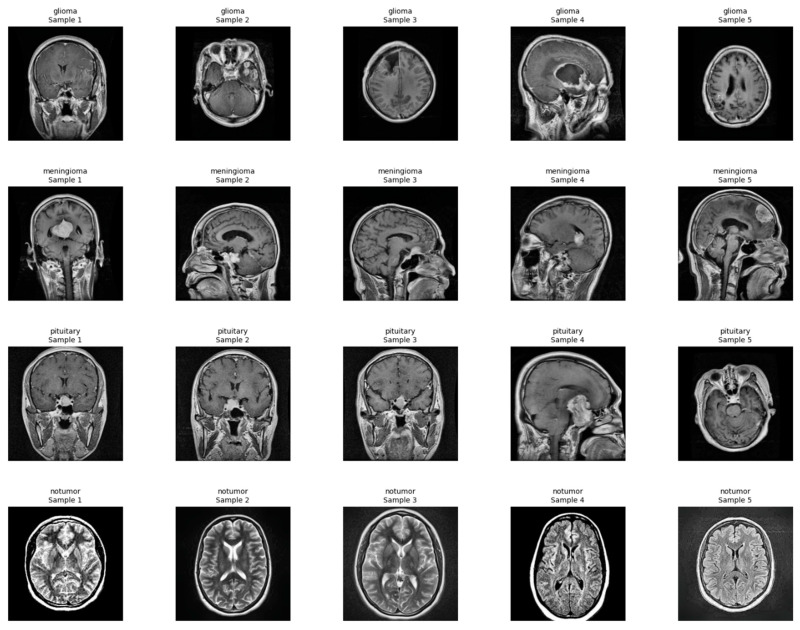

Methods: A diagnosis system was developed combining 2D tumor classification and 3D volumetric segmentation. Classification employed a fine-tuned MobileNetV2 model trained on a glioma, meningioma, pituitary tumor, and normal control dataset. Segmentation employed a SegResNet model trained on BraTS multi-channel MRI with synthetic no-tumor data. A meta-classifier MLP was used for binary tumor detection from volumetric features. Explainability was offered using XRAI maps for 2D predictions and Gaussian overlays for 3D visualizations. The platform was incorporated into a web interface for clinical use.

Results: MobileNetV2 2D model recorded 98.09% classification accuracy for tumor classification. 3D SegResNet obtained Dice coefficients around 68-70% for tumor segmentations. The MLP-based tumor detection module recorded 100% detection accuracy. Explainability modules could identify the area of the tumor, and saliency and overlay maps were consistent with real pathological features in both 2D and 3D.